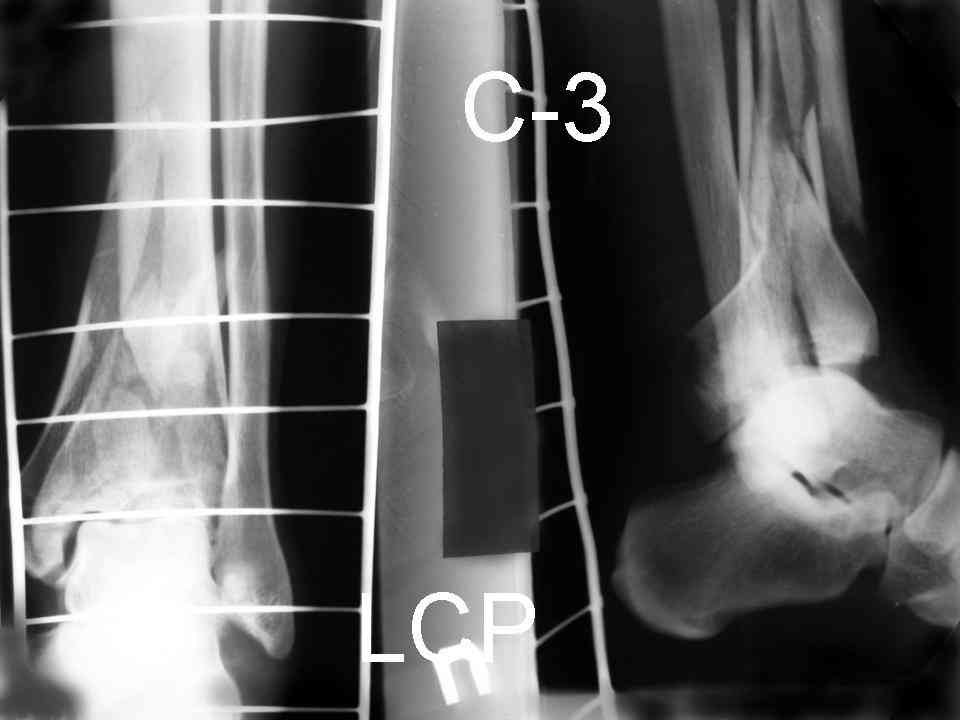

Послала ещё два снимка, если не пройдут, пошлю ещё. Дрягин. Если есть вопросы, готов ответить.